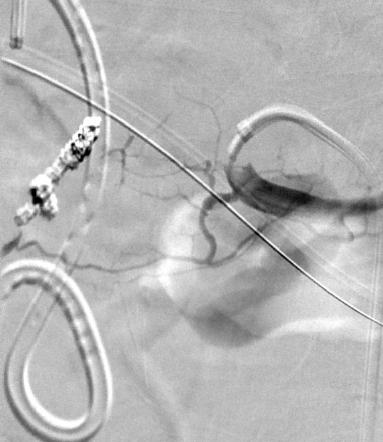

主动脉支撑架植入后II型内漏 |

选择性右髂腰动脉造影显示内漏来自于该动脉 |

右髂腰动脉NBCA栓塞术

(NBCA : Lipiodol = 1 : 4)

经肠系膜上动脉-结肠中动脉-肠系膜下动脉选择性动脉造影显示内漏还来自于该动脉 |